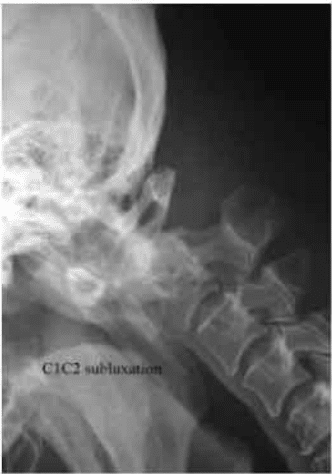

Anterior arch of C1 subluxes anteriorly narrowing the space available for cord. This is seen on MRI scan. The space available for cord widens on neck extension.Investigations

Investigations showed C1-C2 subluxation from Os Odontoid Eum. This was reducible on neck extensions.